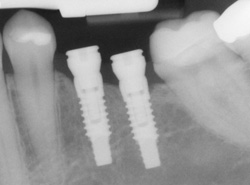

X-ray of an implant in positionModern dental implants are highly reliable and exponentially stronger than the tooth roots they are replacing. Recently, the development of stronger titanium alloys (titanium) and implant-surface technology has dramatically improved dental implant success. Today, dental implants have become the single most successful implantable device in dentistry or medicine.